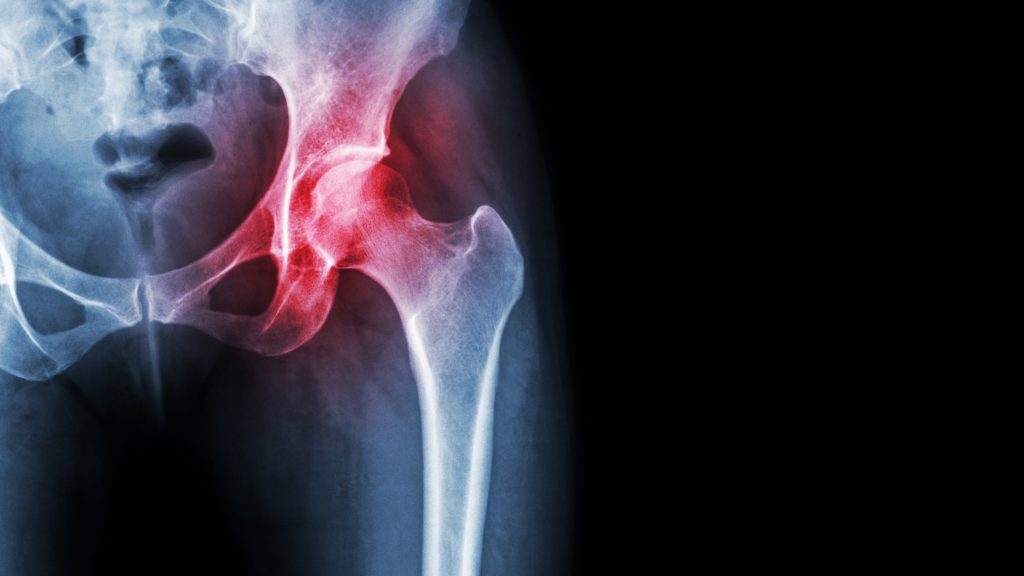

Hüfte mit Coxarthrose

Bei der Coxarthrose, auch unter dem Begriff Hüftarthrose bekannt, handelt es sich um einen fortschreitenden Knorpelverschleiß im Hüftgelenk. Die Knorpelschicht bedeckt eigentlich die Gelenksflächen des Hüftkopfes und der Hüftpfanne, wodurch das reibungslose Gleiten der Gelenkflächen ermöglich wird. Bei der Hüftarthrose nutzt sich der Knorpel aber mit der Zeit zunehmend ab, wird dünner und kann an einigen Stellen sogar reißen. Dadurch kommt es zur Druckerhöhung auf den darunterliegenden Knochen und die Beweglichkeit des Gelenkes lässt nach.

Wird der Gelenkknorpel dünner und der Gelenkspalt schmaler, können Stöße und Belastungen während der Bewegung nicht mehr so gut absorbiert werden und die Druckbelastung der Knochen steigt. Die Ursachen für die Erkrankung sind vielfältig und oftmals eine Kombination von mehreren Faktoren.